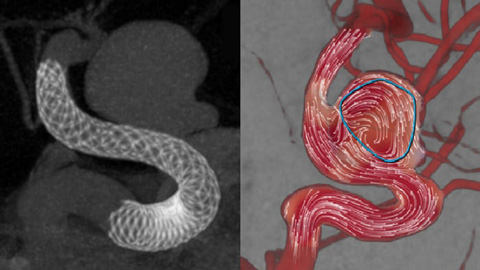

Being able to immediately assess the impact of flow diverters on blood flow is crucial during treatment. AneurysmFlow converts information from a SmartCT Angio acquisition and 2D DSA flow sequences into quantitative flow values. These values are used to visualize and quantify blood flow patterns before and after flow diverter deployment in cerebral aneurysms.

AneurysmFlow helps to visualize and quantify blood flow patterns in the parent vessel and aneurysm sac to obtain key information that can assist deployment of flow diverters and other embolization devices.

AneurysmFlow evaluates changes in blood flow in the aneurysm, by calculating the change in Mean Aneurysm Flow Amplitude (MAFA ratio) before and after flow diverter placement.